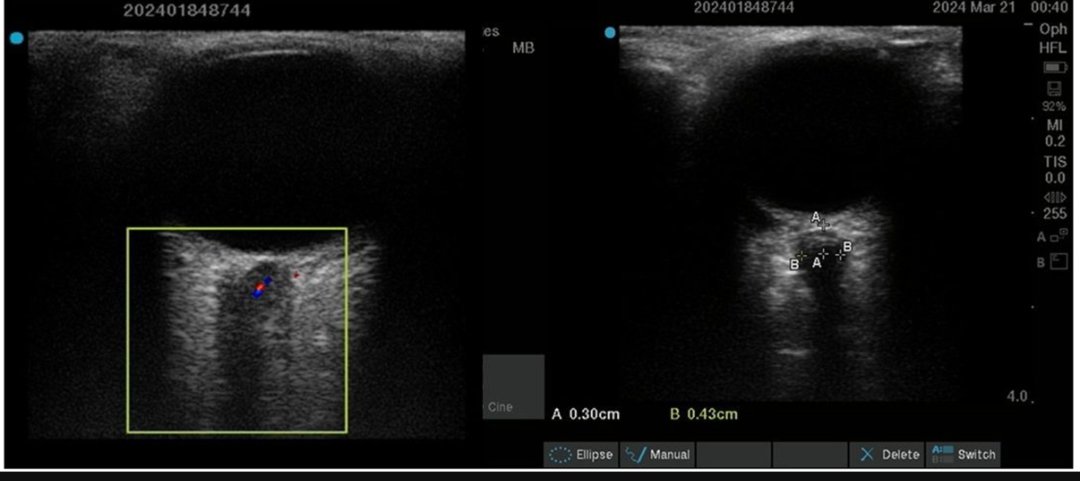

‘Point-of-Care Ultrasound (POCUS) guided volume management... : Hepatology journals.lww.com/hep/abstract/9… Now online. #livertwitter Ajay Duseja Dr Nipun Verma Anand V Kulkarni HEPOCUS (Liver POCUS) Florent Artru Manhal Izzy Elliot Tapper POCUS to classify volume status in Cirrhosis & AKI Trajectory